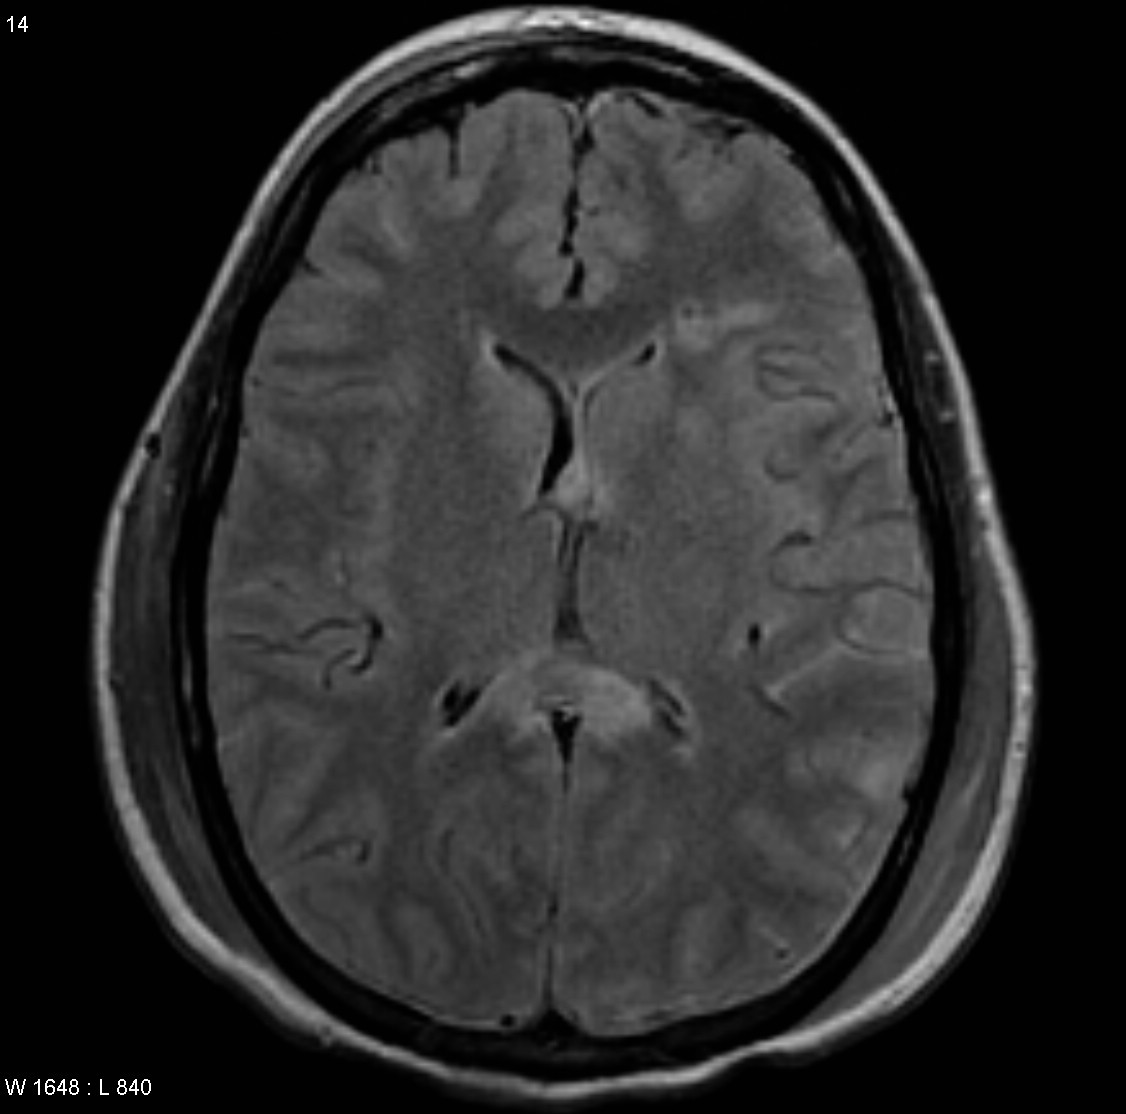

Note the multiple sites of oedema and haemorrhage, involving the brain stem and corpus callosum as well as subcortical white matter and left cerebral peduncle. High FLAIR signal is also seen in the dorsal midbrain. EVD insitu.

Case Discussion

Diffuse axonal injury can be subtle on CT but have devastating consequences for the patient. This is a case of grade III injury (involvement of brainstem) and carries a poor prognosis.

Diffuse axonal injury (DAI), also known as traumatic axonal injury (TAI), is a severe form of traumatic brain injury due to shearing forces. It is a potentially difficult diagnosis to make on imaging alone, especially on CT as the finding can be subtle, however, it has the potential to result in severe neurological impairment.

The diagnosis is best made on MRI where it is characterised by several small regions of susceptibility artifact at the grey-white matter junction, in the corpus callosum, and in more severe cases in the brainstem, surrounded by FLAIR hyperintensity.

Diffuse axonal injury is characterised by multiple focal lesions with a characteristic distribution: typically located at the grey-white matter junction, in the corpus callosum and in more severe cases in the brainstem (see: grading of diffuse axonal injury).

MRI is the modality of choice for assessing suspected diffuse axonal injury even in patients with entirely normal CT of the brain 5,6. MRI, especially SWI or GRE sequences, exquisitely sensitive to paramagnetic blood products may demonstrate small regions of susceptibility artefact at the grey-white matter junction, in the corpus callosum or the brain stem. Some lesions may be entirely non-haemorrhagic (even using high field strength SWI sequences). These will, however, be visible as regions of high FLAIR signal.